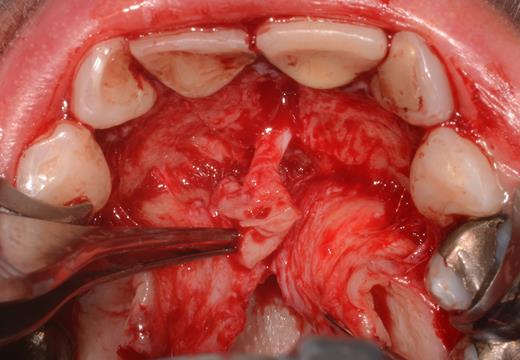

After a sulcular incision on the palatal side from teeth 15 to 25 and an incision in the midline of the palate omitting the incisive papilla and the two orifices of the NPD, two full-thickness mucoperiosteal flaps were raised. Thereafter, the incisive papilla and the whole contents of the incisive canal were enucleated (Figs 4–6). The bony incisive canal was filled with autologous bone harvested from the palatal region (bone scraper) (Fig. 7). A tension-free primary wound closure was achieved by moving the palatal flaps to the midline using single button and interdental vertical mattress sutures (Monocryl 4-0, Ethicon, Johnson & Johnson, USA) (Fig. 8). To avoid wound dehiscence and hematoma, an iodoforme gauze and a palatal plate were applied (Fig. 9). The patient was instructed to rinse three times a day with 0.1% chlorhexidine (formula hospitalis) for 2 weeks postoperatively. Sutures were removed after 14 days.

Preparation of the soft tissue of the incisive canal and the incisive papilla.

Situation after removal of the entire soft tissue contents of the incisive canal.